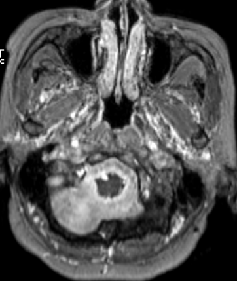

2015-4-1 MRI

2015-4-1

2015-4-3